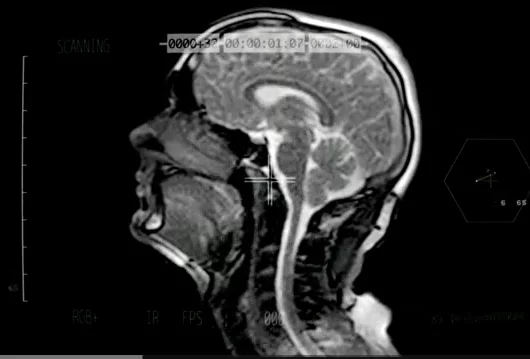

Sivu, muzyk z Londynu stworzył teledysk... filmując pracę swojego mózgu w czasie śpiewania piosenki. Piosenkarz śpiewał utwór "Better Man Than He" podłączony do skanera MRI - podaje tvn24.pl.

Teledysk jest jednocześnie formą promocji badań nad wrodzonym rozszczepem wargi i podniebienia, które prowadzi St Bartholomew’s Hospital w Londynie. Skaner MRI, do którego podłączony był Sivu w czasie śpiewania to narzędzie do diagnozowania zmian w twarzoczaszce.

Skan mózgu piosenkarza został po zarejestrowaniu poddany obróbce przez reżysera Adama Powella i specjalistę od efektów specjalnych Lewisa Kyle'a White'a, którzy stworzyli teledysk z nagrań. - Chciałem dać fanom małą niespodziankę w postaci oszałamiającego wideo. Zwłaszcza, że to mój pierwszy teledysk w karierze. Zgoda na to, by wszyscy zajrzeli do mojego mózgu, jest czymś niesamowitym - mówił o swoim projekcie Sivu, który zyski z oglądania umieszczonego na YouTube wideo ma zamiar przeznaczyć na badania nad rozszczepem wargi i podniebienia u dzieci.